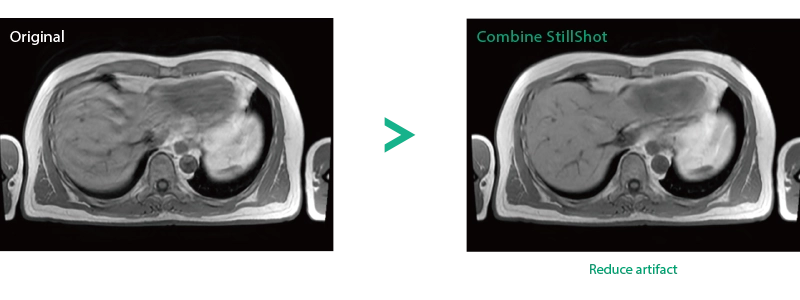

Imperfect imaging data to be better image quality through post-processing

By providing functions to remove and suppress artifacts in the imaging data and to generate reconstructed images from limited imaging data, it reduces the re-imaging rate and supports the realization of smooth MRI examinations.

Reduce artifacts caused by patient movement, such as coughing or sneezing, by post reconstruction.

Improving SNR and reducing wrap-around artifact through post reconstruction.

When motion artifacts occurs in the image due to coughing, sneezing, or involuntary movements, either or both the visual information acquired by monitoring cameras, Synergy Vision, and the intrabody information acquired by the navigator pulse can be used to provide an image with reduced artifacts. This reduces the re-imaging rate.

Body movements that affect image quality are detected from monitoring cameras based on thresholds derived for each body part.

Movements within the body are detected by navigator pulses. Body movements that significantly affect image quality are detected based on the error between pulses.